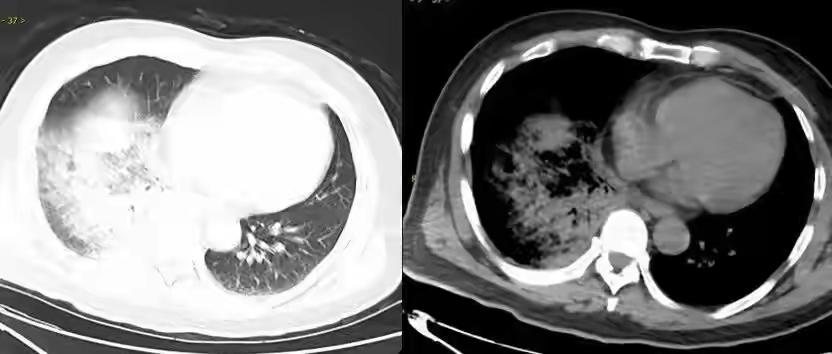

半月前,福建46岁司机林师傅(化名)养了一只鹦鹉,因开车不便照顾,便将鹦鹉揣在口袋里随身带,开车间隙逗玩。 没过几天,他突发高烧至38.7℃,伴寒战、干咳、乏力,自行吃感冒药后体温反复,还出现头晕头痛、反应迟钝,精神状态极差。 林师傅被家人送医就诊,检查显示,其肝肾功能受损,炎症指标大幅超标。医生追问病史,得知其“口袋养鹦鹉”习惯,经进一步检查确诊为鹦鹉热衣原体。 这位林师傅的情况提醒我们,宠物的养护不仅仅是日常陪伴,还涉及到潜在的健康风险。鹦鹉热(鸟源性疾病)是由鹦鹉热衣原体(Chlamydia psittaci)引起的人畜共患病,常通过接触感染鸟类的粪便、羽毛或分泌物传播给人。 【关于鹦鹉热衣原体】: 传播途径:主要通过吸入被污染的尘埃或飞沫,接触感染鸟类的排泄物、羽毛或分泌物。 潜伏期:通常为1到3周。 症状:发热、寒战、头痛、乏力、干咳、肌肉疼痛,有时伴有肝肾功能异常,严重者可能出现肺炎或其他并发症。 【预防措施】: 避免与鸟类的粪便、羽毛直接接触,尤其是在未采取防护措施时。 对宠物鸟定期进行健康检查。 在处理鸟类或其排泄物时佩戴口罩和手套。 保持良好的个人卫生,勤洗手。 【诊断与治疗】: 若怀疑鹦鹉热,应及时就医,进行血清学检测或PCR检测。 一般采用抗生素治疗(如多西环素)效果较好。 早期诊断和治疗能有效预防严重并发症。 林师傅的案例提醒宠物主人应注意养鸟的健康风险,避免将鸟类带在口袋或随身携带,尤其是在开车或从事其他可能引起意外的活动时。养宠物虽带来快乐,但也要确保安全与健康,定期检查、合理接触,减少疾病传播的风险。鹦鹉护理 鹦鹉生病